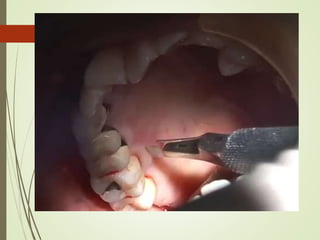

1. CLASSICAL TECHNIQUE

9/25

MODIFICATION OF THE RECIPIENT BED

10/25